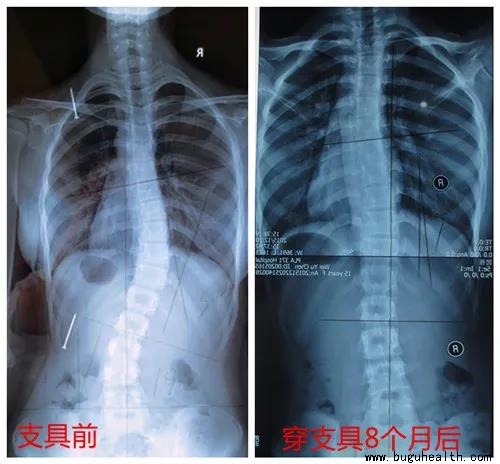

布骨医学科普:脊柱侧弯之孩子佩戴支具有用吗?

保守治疗脊柱侧弯,主要是依靠支具和矫形体操,其他方法都是辅助。

一般,对于cobb角在20°以上,并且还在长身体的发育高峰期孩子都会建议使用支具治疗,很多家长也都有了解到带支具对孩子的脊柱侧弯有矫正作用,但是却忽略了一个问题,那就是,您孩子戴的支具有一定效果,但是矫正效率究竟如何,能达到50%的矫正率吗?

第一步,测量角度,进行戴支具前后的对比。

不戴支具与戴支具对比:

如图所示,从左到右看,度数从腰左弯18°矫正到腰右弯5°,中线左边的椎体在支具内矫正到中线右边。度数和中线都过矫,这是带上支具最理想的结果不过,大部分孩子很难实现双过矫。当双过矫不能实现时,先实现中线过矫,度数尽量减少。